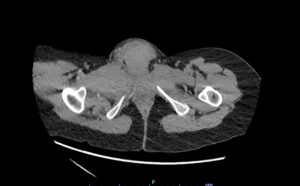

Vulvar Hematoma. CT Axial, Unannotated. JETem 2024

Vulvar Hematoma. CT Axial Unannotated. JETem 2024